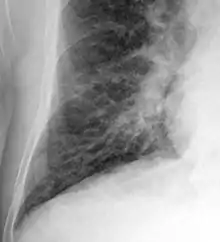

Chest X-ray

Chest X-rays are frequently used to aid in the diagnosis of CHF. In a person who is compensated, this may show cardiomegaly (visible enlargement of the heart), quantified as the cardiothoracic ratio (proportion of the heart size to the chest). In left ventricular failure, evidence may exist of vascular redistribution (upper lobe blood diversion or cephalization), Kerley lines, cuffing of the areas around the bronchi, and interstitial edema. Ultrasound of the lung may also be able to detect Kerley lines.[72]

Congestive heart failure with small bilateral effusions

Kerley B lines